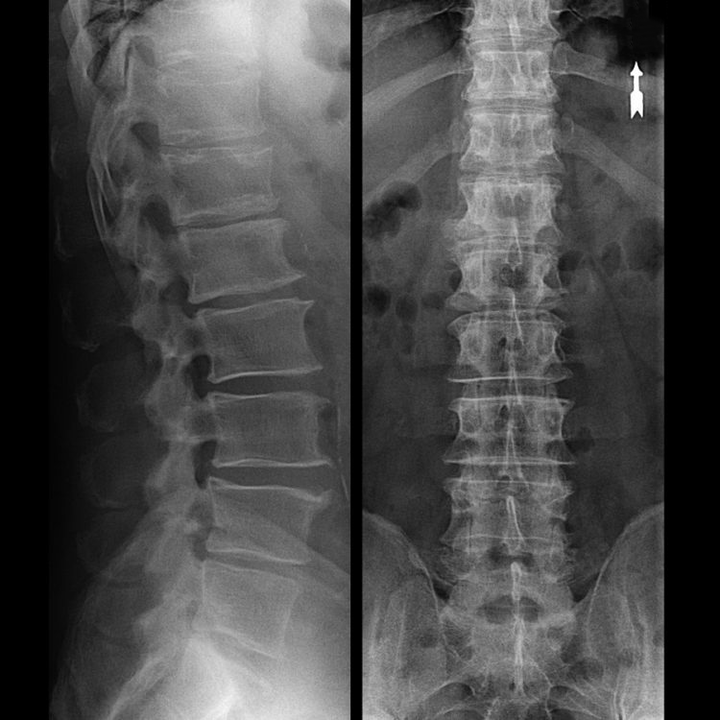

In typical cases, osteochondrosis of the cervical and cervical-thoracic spine occurs as described above.Therefore, the main stage of diagnosis was and remains the identification of the patient's complaints, establishing the presence of concomitant muscle spasm by simple palpation of the muscles along the spine.Is it possible to confirm the diagnosis of osteochondrosis by X-ray examination?

An “X-ray” of the cervical spine, and even with functional tests of flexion and extension, does not show cartilage, since its tissue transmitsand dehydrated.Functional testing can confirm the diagnosis of cervical spine instability.

Since the discs themselves can only be seen using CT or MRI, MRI and X-ray CT are indicated to clarify the internal structure of the cartilage and formations such as bulges and hernias.Thus, with the help of these methods, an accurate diagnosis is made and the result of the tomography is an indication, and even a topical guide, for the surgical treatment of a hernia in the neurosurgery department.